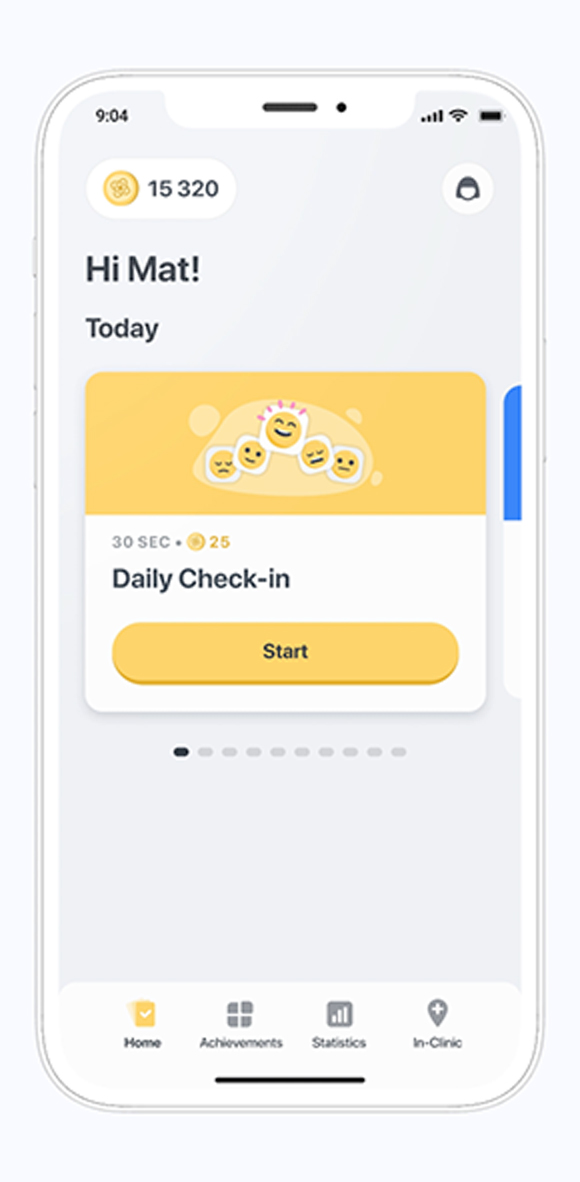

The Konectom mobile application is designed for all smartphones in multiple languages following medical device development standards.

At this stage, we are focused on demonstrating the value of Konectom in a research setting for several neurological diseases. Only study participants are granted access.

The Konectom mobile application is designed for all smartphones in multiple languages following medical device development standards.

The Konectom mobile application is designed for all smartphones in multiple languages following medical device development standards.